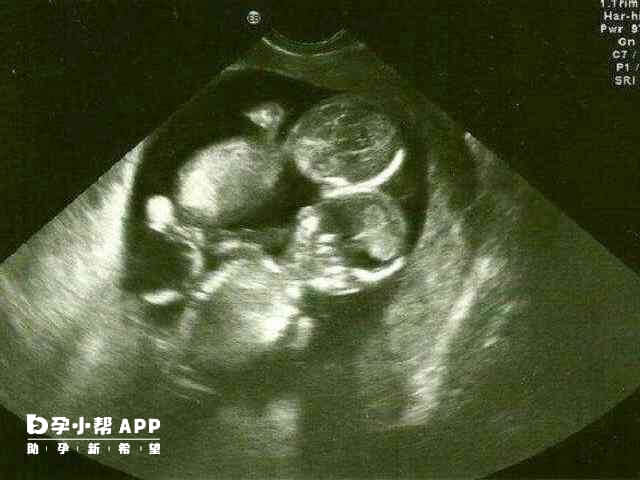

怀上双胞胎是一件可遇不可求的事情,而很多的人认为怀双胞胎是一件高兴地事情,但是过于片面,不能只看到好的没有看到坏的一面。比如说怀双胞胎比怀单胞胎受的苦要多很多的,而且孕期出现高血压、高血糖、早产、流产的几率是比较高的。就比如单单在饮食方面,需要注意的事情就很多,不能像单胎孕妈妈那么“肆意”,这里就关于怀上双胞胎之后的饮食问题,给各位妈妈提几点建议。